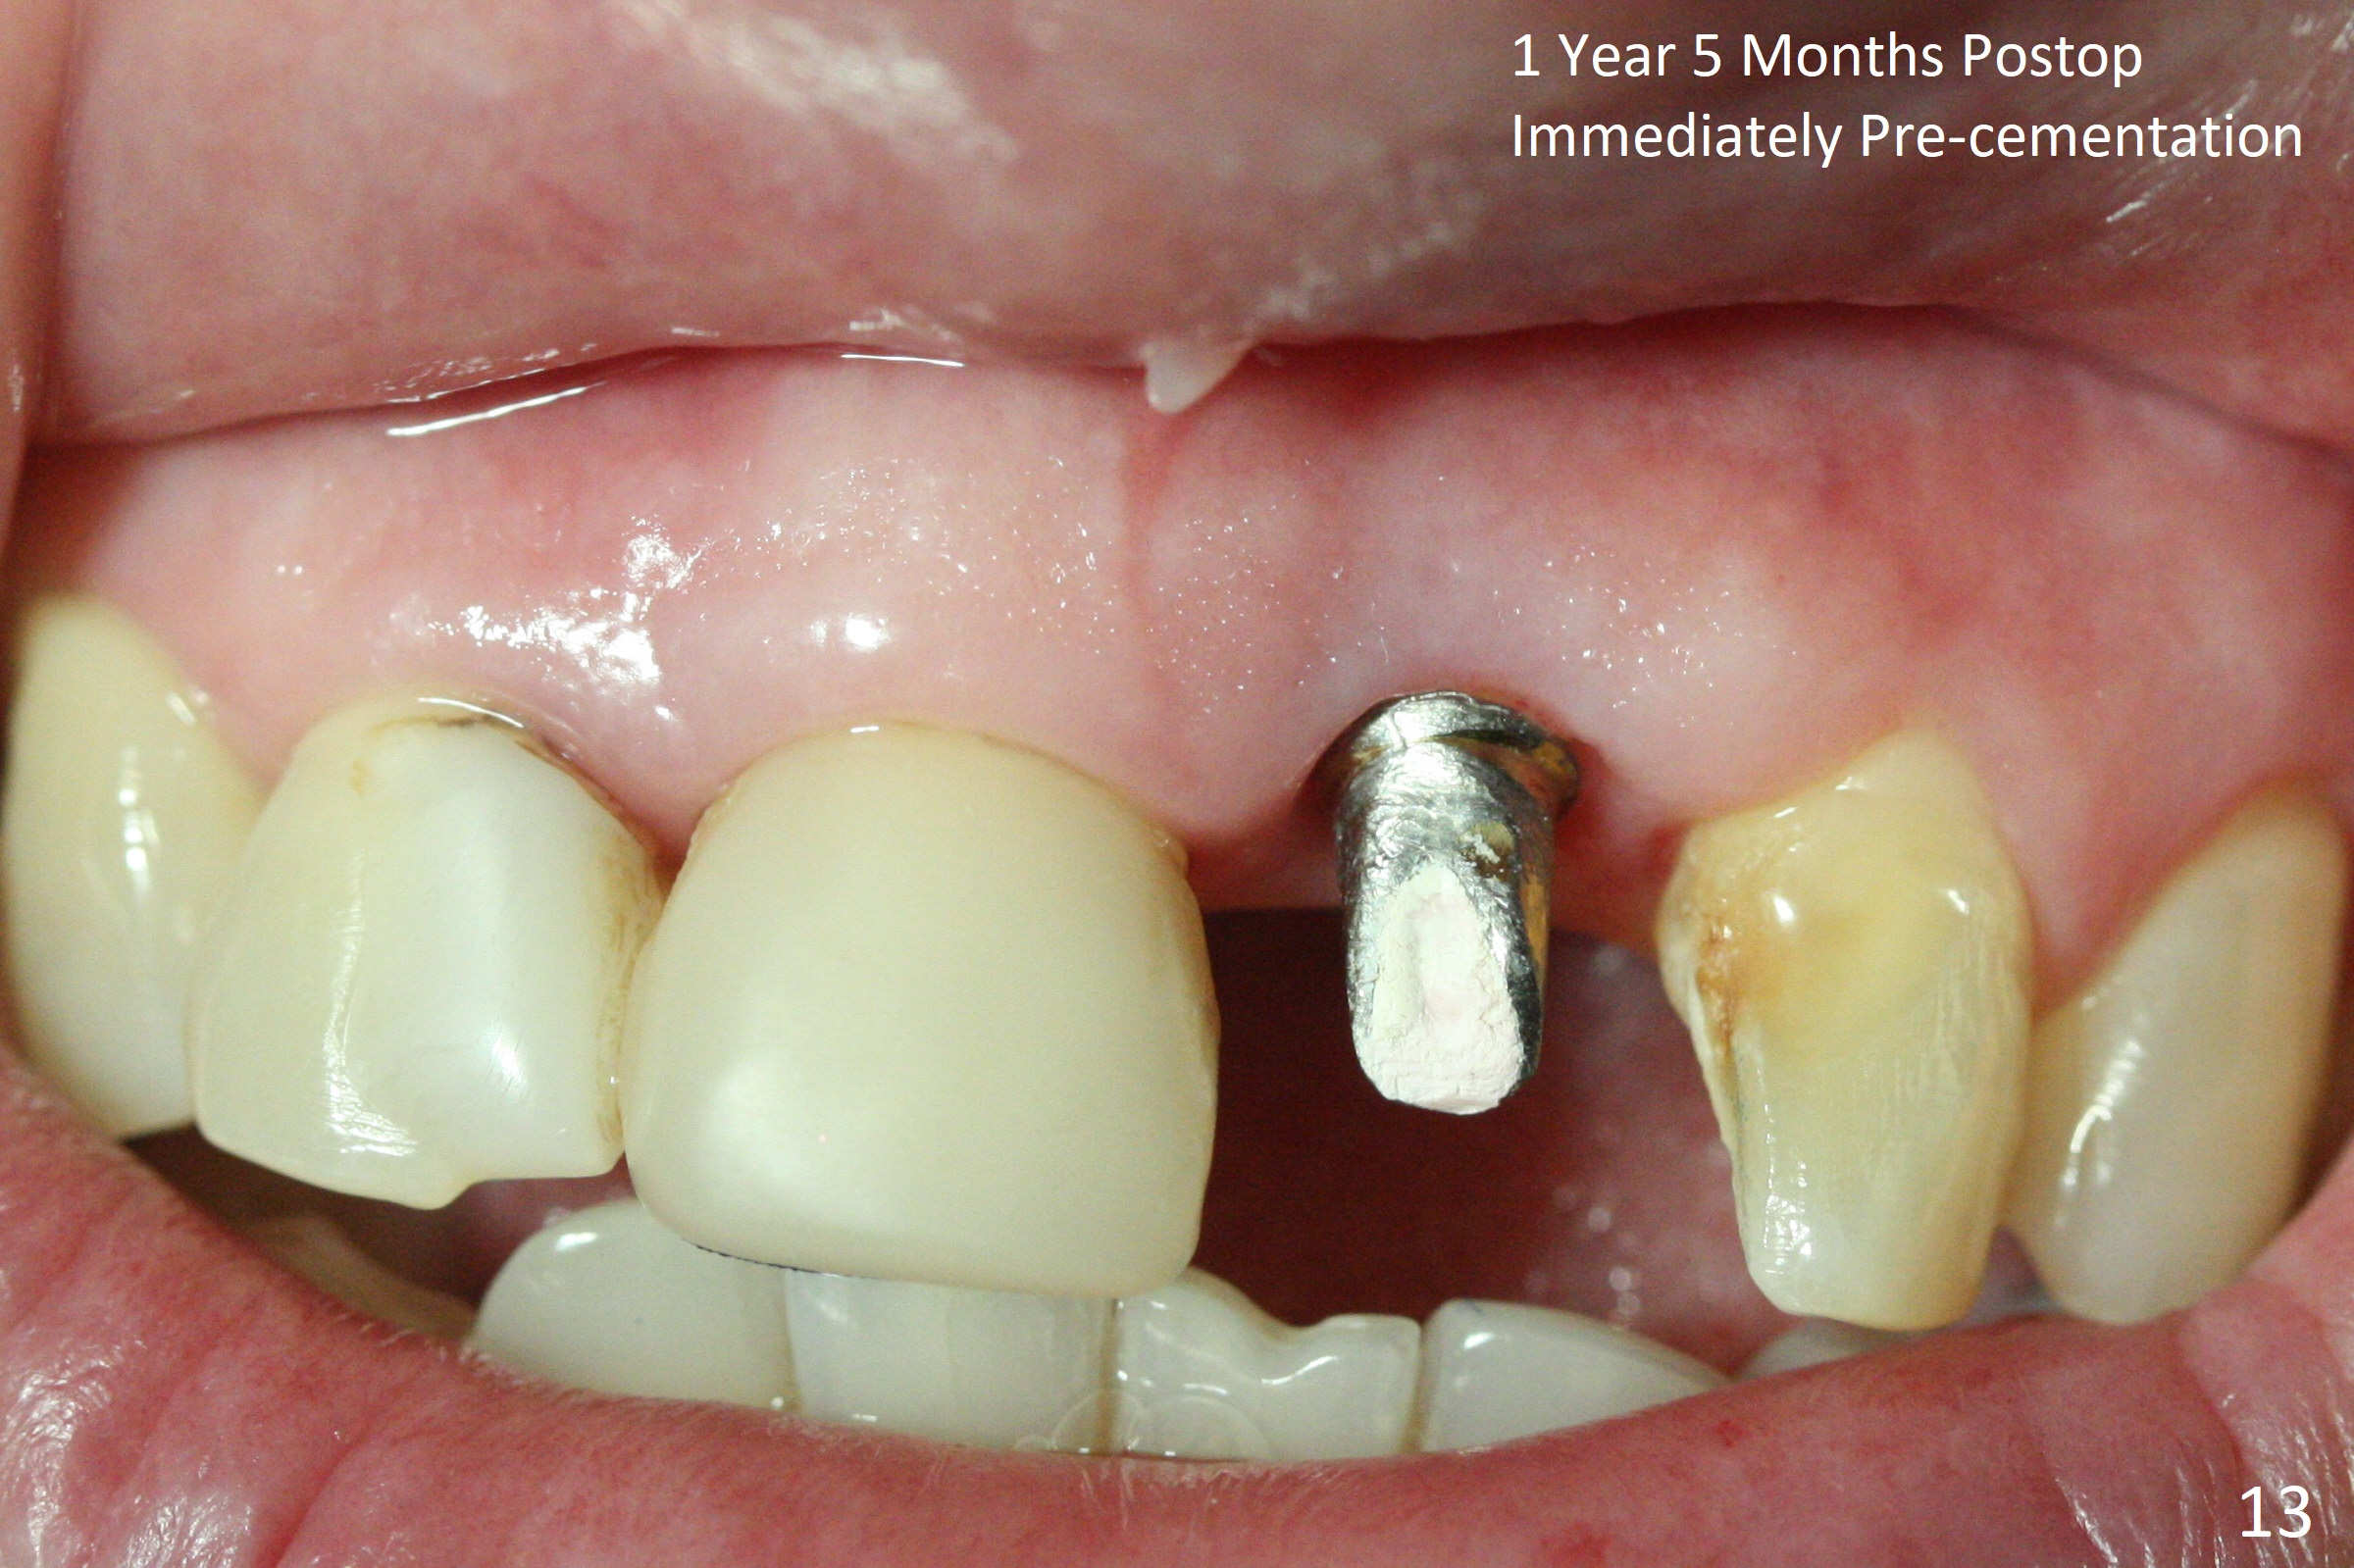

In spite of the incisobuccal shift of the tooth #9 with gingival recession (Fig.1) and loss of the buccal plate (intraop finding), there is no buccal contour collapse (Fig.2 *), due to the presence of the buccal bone of the neighboring teeth and the root of the affected tooth. After extraction, osteotomy (Fig.3) and dummy implant try in (Fig.4), a definitive implant is placed palatally with the buccal gap (Fig.5 *). In fact there is mild buccal contour collapse prior to bone graft (Fig.5 arrow). When allograft (Vera, Fig.6,7 *) is packed buccal to the implant and overlying abutment as a solid support, the buccal contour seemingly returns normal (Fig.6 arrowhead). An immediate provisional is fabricated to prevent loss of the bone graft during healing period. Bone graft kept in place by the provisional turns yellow 6 days postop (Fig.8). The buccal plate remains strong, while the fistula becomes indistinguishable. After adjustment of the provisional margin a few times (nearly 3 months postop, Fig.9,10), the gingival margin appears to have grown incisally, as compared to Fig.1. There is minimal buccal bone collapse (Fig.10). Dislodgement of the abutment and provisional forces her to return 1 year 4 months postop; the socket has healed (Fig.11). The buccal plate is not concave 1 year 4 months postop (Fig.12). The gingiva is slightly recessive (Fig.13) with mild buccal plate concavity (Fig.14) immediately before cementation. The implant could be placed ~ 1 mm deeper (Fig.15).